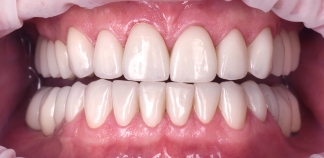

До лечения

Жалобы на цвет и форму зубов.

Как лечили

Установлены коронки на зубы.